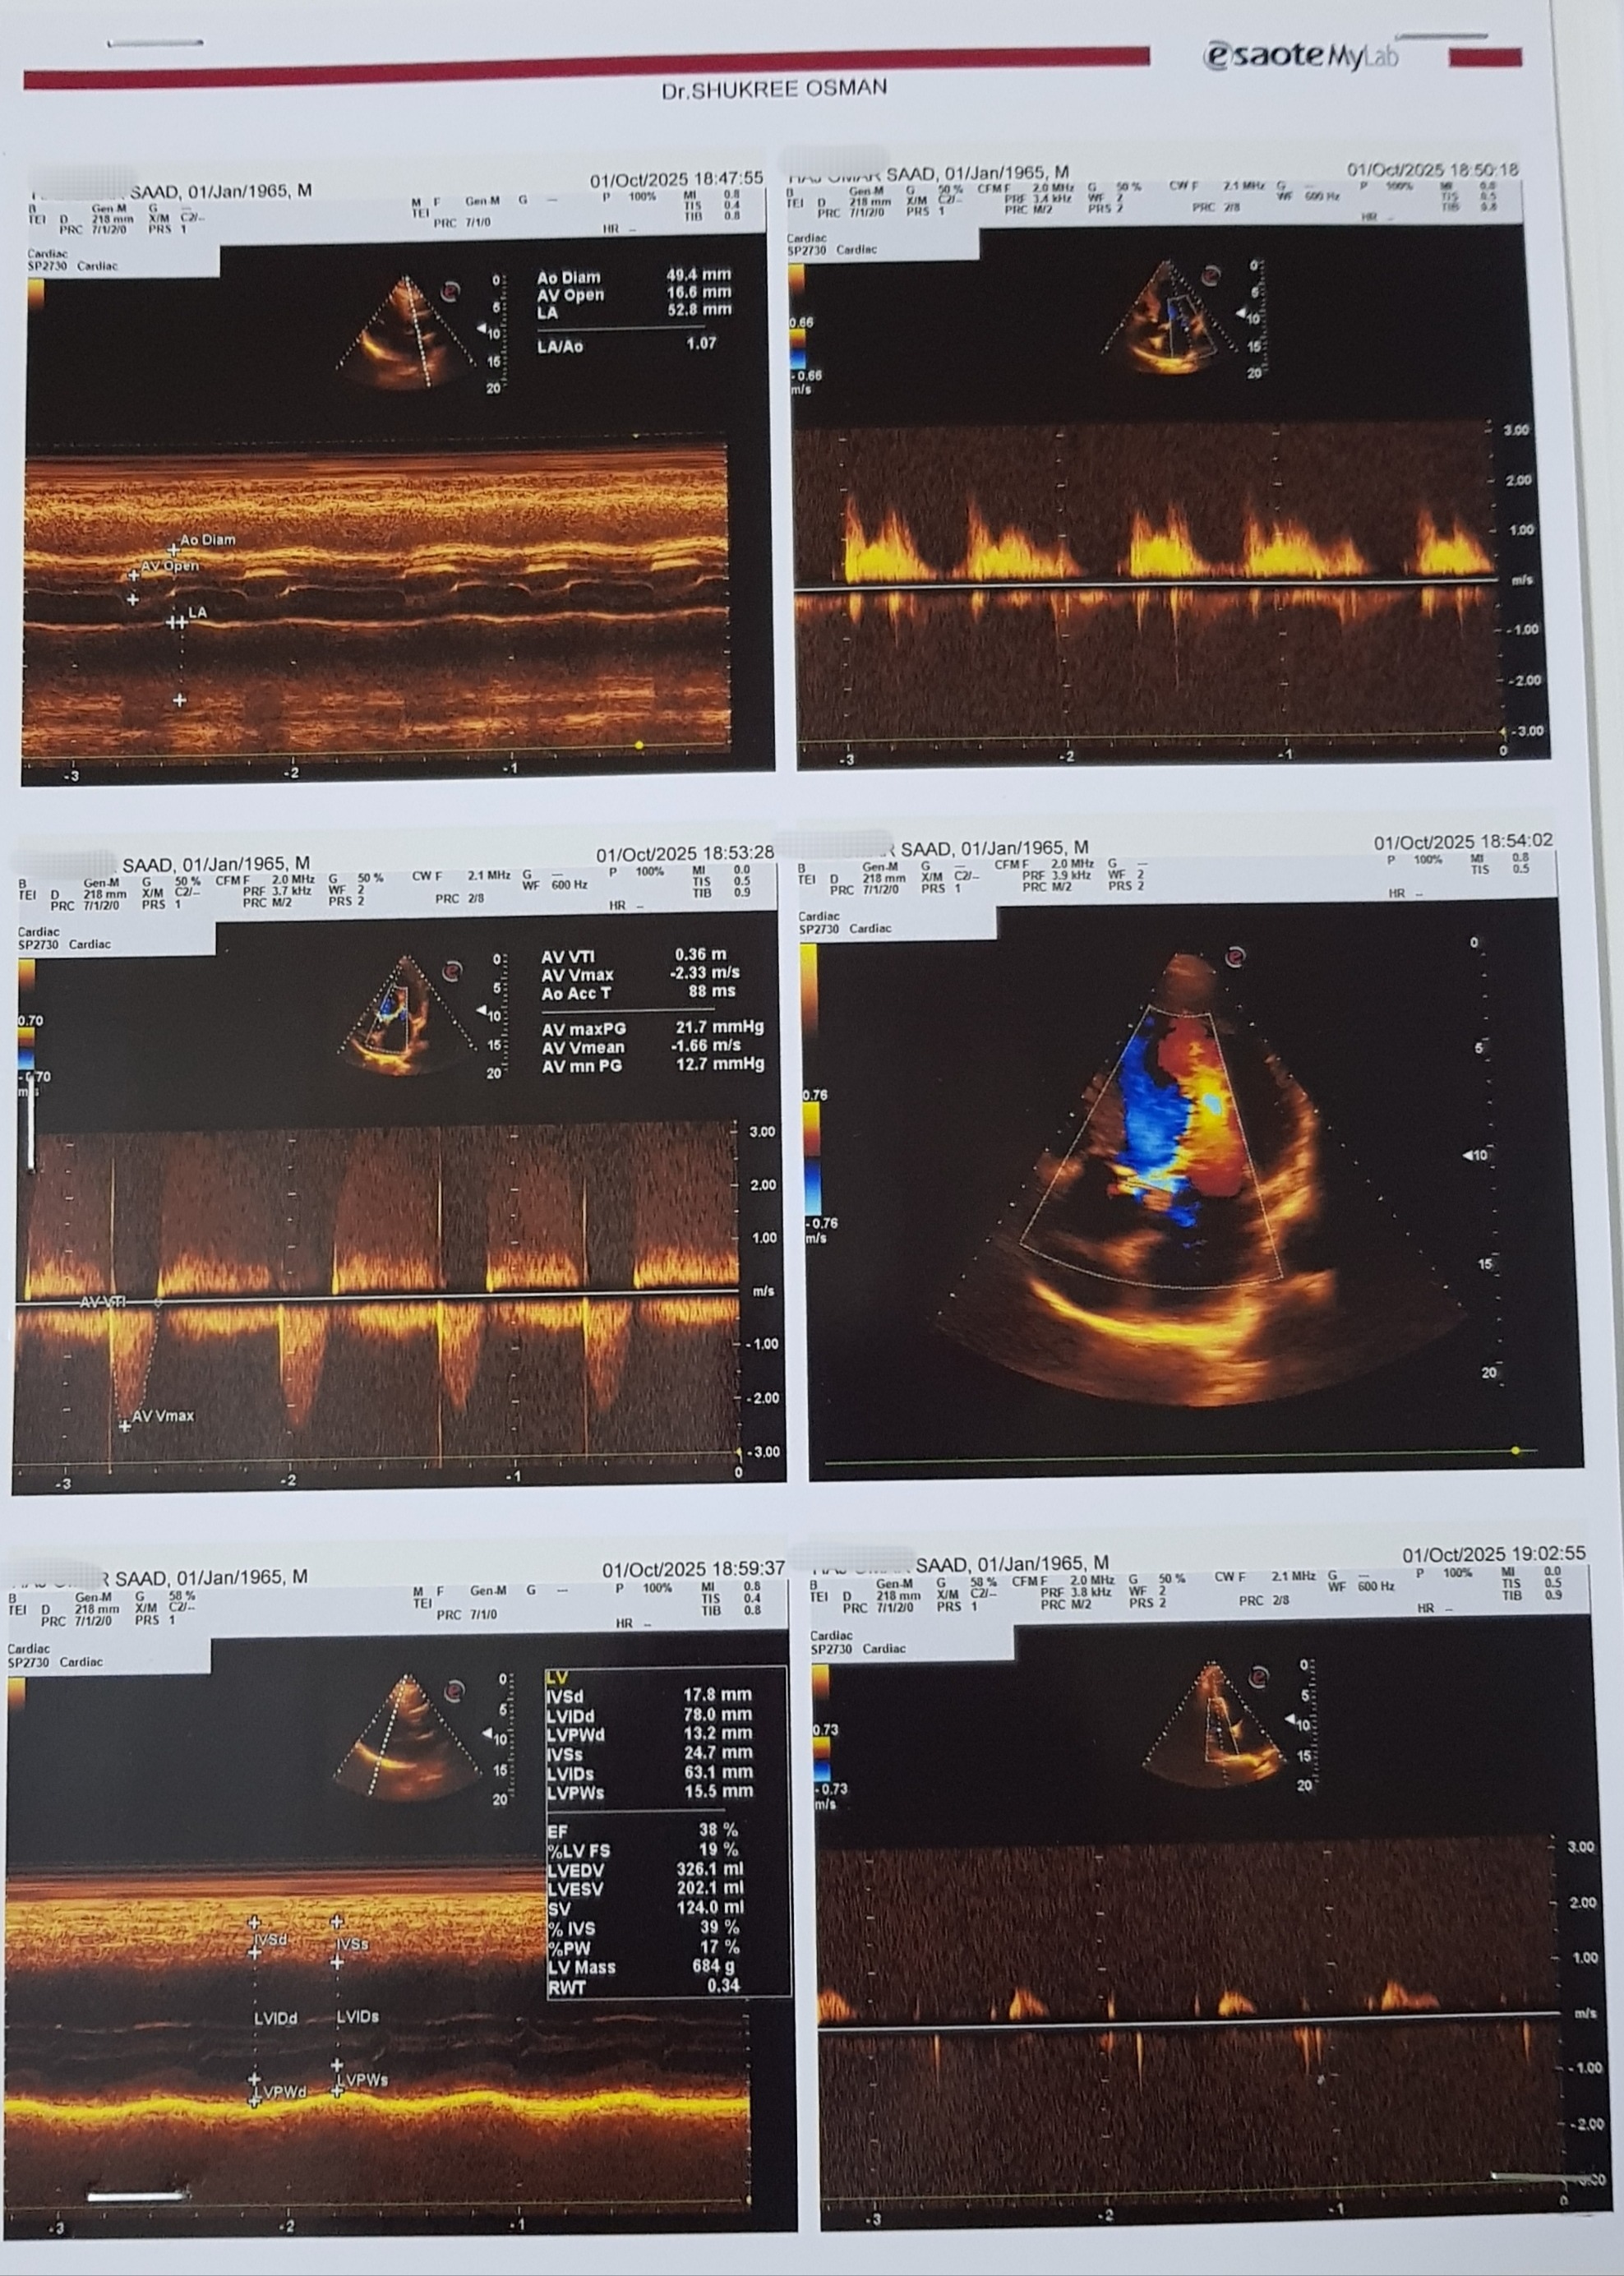

First image : The Doppler echocardiogram report for my father's heart, Its translated using Google translate to English .